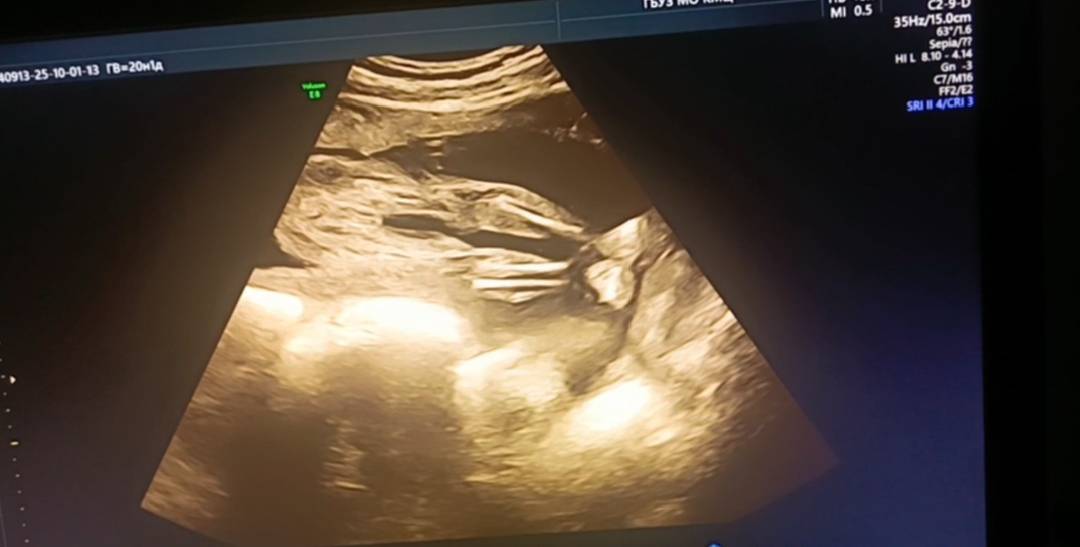

Доброй ночи. Девочки. Может кто понимает, врач не сказал точно мальчик или девочка. Была на 2 скрининге, а он сложился и не показывал. Может кто , что увидит и поймет кто у нас в итоге)

Вроде девчонка . УЗИ мальчишек видела там прям треугольники хорошие, а мне с девочкой сказали: видите три полоски - это девочка

Я если честно не поняла про какие полоски речь , но чисто в теории тут тоже полоски 😅

Может писюля наверх?! Яички опускаются к родам, поэтому там кожица снизу ещё.